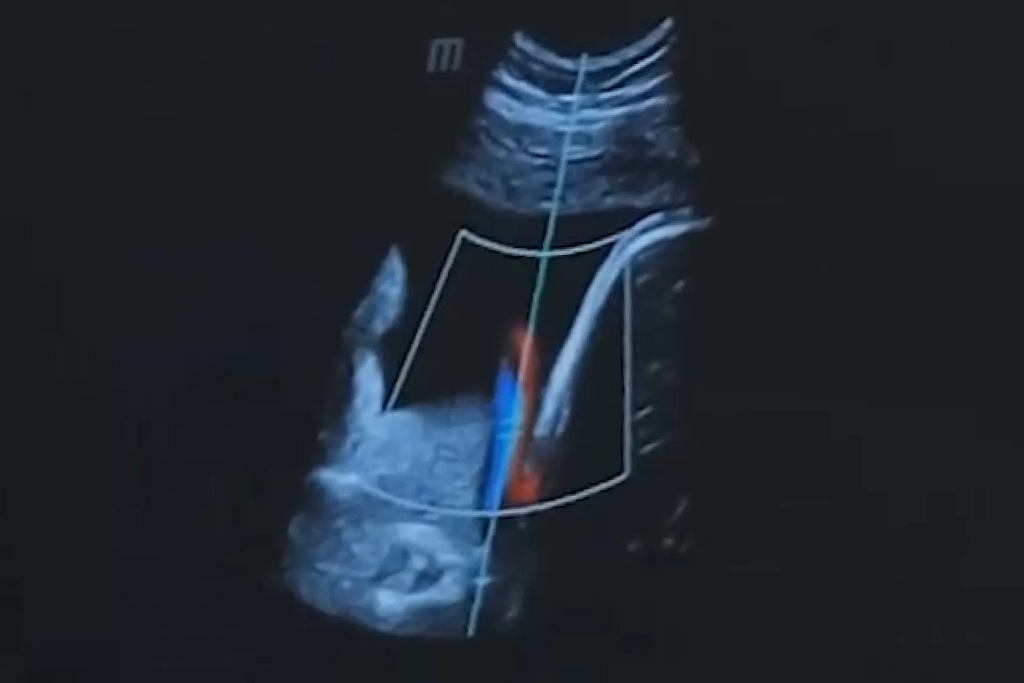

Роль режима тканевой гармоники в медицинской диагностике, несомненно, критическая. Этот метод ультразвукового исследования обеспечивает высокую разрешающую способность, позволяя врачам более точно выявлять структурные изменения в органах и тканях. Применение тканевой гармоники в онкологии, например, значительно повышает точность обнаружения опухолей и улучшает оценку их характеристик.

В кардиологии режим тканевой гармоники активно используется для более точной оценки функции сердца и выявления структурных изменений в миокарде. Это содействует более эффективной диагностике и планированию лечения сердечно-сосудистых заболеваний.

Например, пациентка с избыточной массой тела обратилась к врачу с жалобами на боли в животе. При обследовании в таком формате медик смог выявить опухоль печени. В данном случае режим тканевой гармоники позволил поставить диагноз, который был бы трудно различим при обследовании в традиционном режиме.

Примером успешного применения тканевой гармоники является диагностика опухолей. Этот режим позволяет более четко выделить границы опухоли и оценить ее структуру, что существенно упрощает планирование хирургического вмешательства.

В случае кардиологии, тканевая гармоника позволяет детально изучать состояние сердечной мышцы, обеспечивая более точную оценку функциональных изменений. Это имеет важное значение при выборе оптимального лечения сердечно-сосудистых заболеваний.